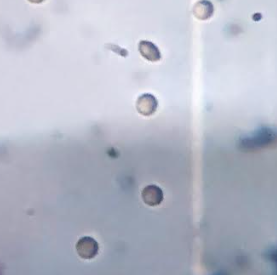

Hemolysis study

Hemolysis study helps to study the effect of the formulation on cell lysis, particularly RBC lysis. PPI dendrimers cause hemolysis due to terminal amine groups of dendrimers. The drug FPV also induces hemolytic anemia as reported by the Food and Drug Administration (FDA) [15]. The plain drug showed very high hemolytic activity (47.07±1.28%). The hemolytic tendency of the drug and dendrimer drastically changed on conjugation. Upon conjugation free drug was not available that reduces the toxicity and thus, RBCs lysis similarly the terminal amine group of dendrimers was occupied by the drug reducing its toxicity. Fig. 8 represents the % hemolysis data of the drug FPV, 5G PPI dendrimers, and three different concentrations of FPV-DEN.

The percentage hemolysis of the formulation was tested at three different levels, demonstrating that toxicity increased with the dose of the formulation [39-41]. The toxicity of the formulation increases as the formulation's concentration rises. At the formulation concentrations of 0.3, 0.6, and 0.9 µg/ml, the toxicity was found to be 5.45±0.99%, 12.12±1.25%, and 22.82±1.08% [22, 23]. RBCs were photographed after being exposed to various formulation concentrations, FPV, as well as saline and water. When RBCs were treated with 0.9% saline, the images revealed no lysis; however, full lysis was shown when RBCs were treated with water. The formulation at a lower concentration (0.3% µg/ml) does not show hemolysis, while hemolysis increases with increasing concentration. Fig. 9 represents the photograph of RBCs treated with saline, water, drug FPV, 5G PPI dendrimers, and FPV-DEN at 0.3%, 0.6%, and 0.9% µg/ml concentration.

(a) Saline (b) Water

(c) FPV (d) 5G PPI Dendrimers

(e) FPV-DEN (0.3 µg/ml) (f) FPV-DEN (0.6 µg/ml)

(g) FPV-DEN (0.9 µg/ml)

Fig. 9: Surface morphology of RBCs-(a) Saline, (b) Water, (c) Drug FPV, (d) 5G PPI dendrimers, (e) FPV-DEN (0.3 µg/ml), (f) FPV-DEN (0.6 µg/ml), and (g) FPV-DEN (0.9 µg/ml)